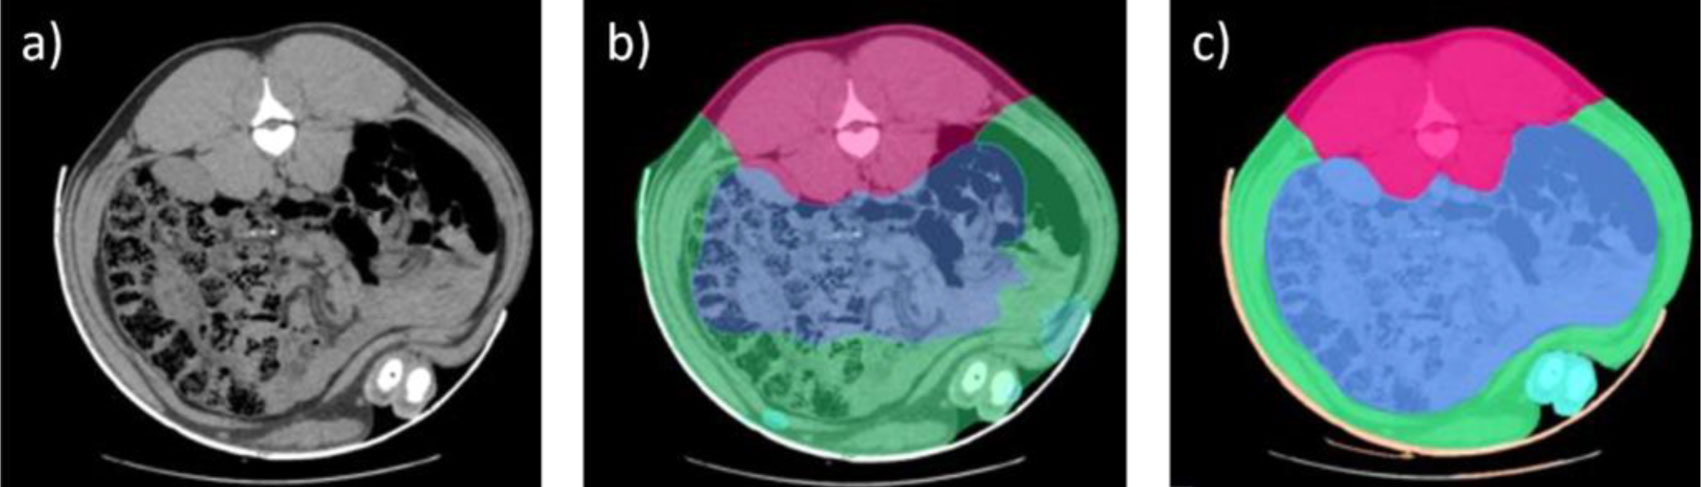

Trong nhiều năm, việc phân tích hình ảnh được thực hiện thủ công, bằng cách xác định thủ công các vùng giải phẫu và loại mô khác nhau (xương, mỡ và cơ), đây đã được xem là một bước tiến lớn. Đến năm 2016, một phương pháp phân tích hình ảnh CT tự động hơn được triển khai, giúp phân biệt được các phần cắt chính như đùi, vai, lưng và ba rọi.

Sự xuất hiện của công nghệ trí tuệ nhân tạo (AI) đóng vai trò then chốt trong việc tự động hóa quy trình này, tạo nền tảng để mở rộng quy mô ứng dụng, tăng số lượng heo được phân tích và nâng cao hiệu quả xử lý dữ liệu.

Tuy nhiên, AI cần được “huấn luyện” trước, nghĩa là phải có một cơ sở dữ liệu khổng lồ các hình ảnh CT đã được phân tích để làm mẫu tham chiếu. Trong trường hợp này, nguồn dữ liệu quý giá đó đã có sẵn nhờ nhiều năm tích lũy hình ảnh CT trước đây, trong đó đã đạt được tiến bộ đáng kể trong phân tách mô và xác định voxel (đơn vị nhỏ nhất cấu thành hình ảnh ba chiều, tương tự như pixel trong ảnh hai chiều) thuộc các loại mô khác nhau.